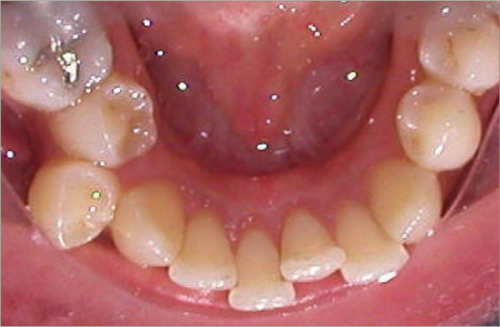

32 year old female:

Diagnosis:

- Previously lost upper first molars

- Severe lower arch crowding

- Midline discrepancy

- Narrow upper arch form

Treatment:

- Extraction of lower right first bicuspid

- Substitution of upper second molars for first molars

- Full fixed appliances

- 23 months